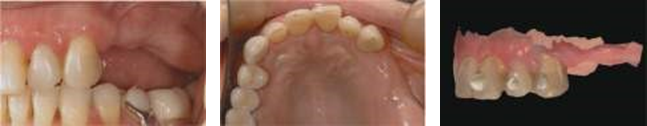

(а)                                                  (б)                                                 (в)

image020.png

(г)                                                      (д)                                                (е)

image024.png

Рисунок 3: Операция и немедленная временная установка: (а) хирургический шаблон в нужном положении; (б) подготовка хирургических мест; © установка имплантата; (d) все имплантаты устанавливаются безлоскутным способом; (e) временная реставрация из ПММА устанавливается на временные титановые абатменты; (f) временный ПММА привинчен к имплантатам.